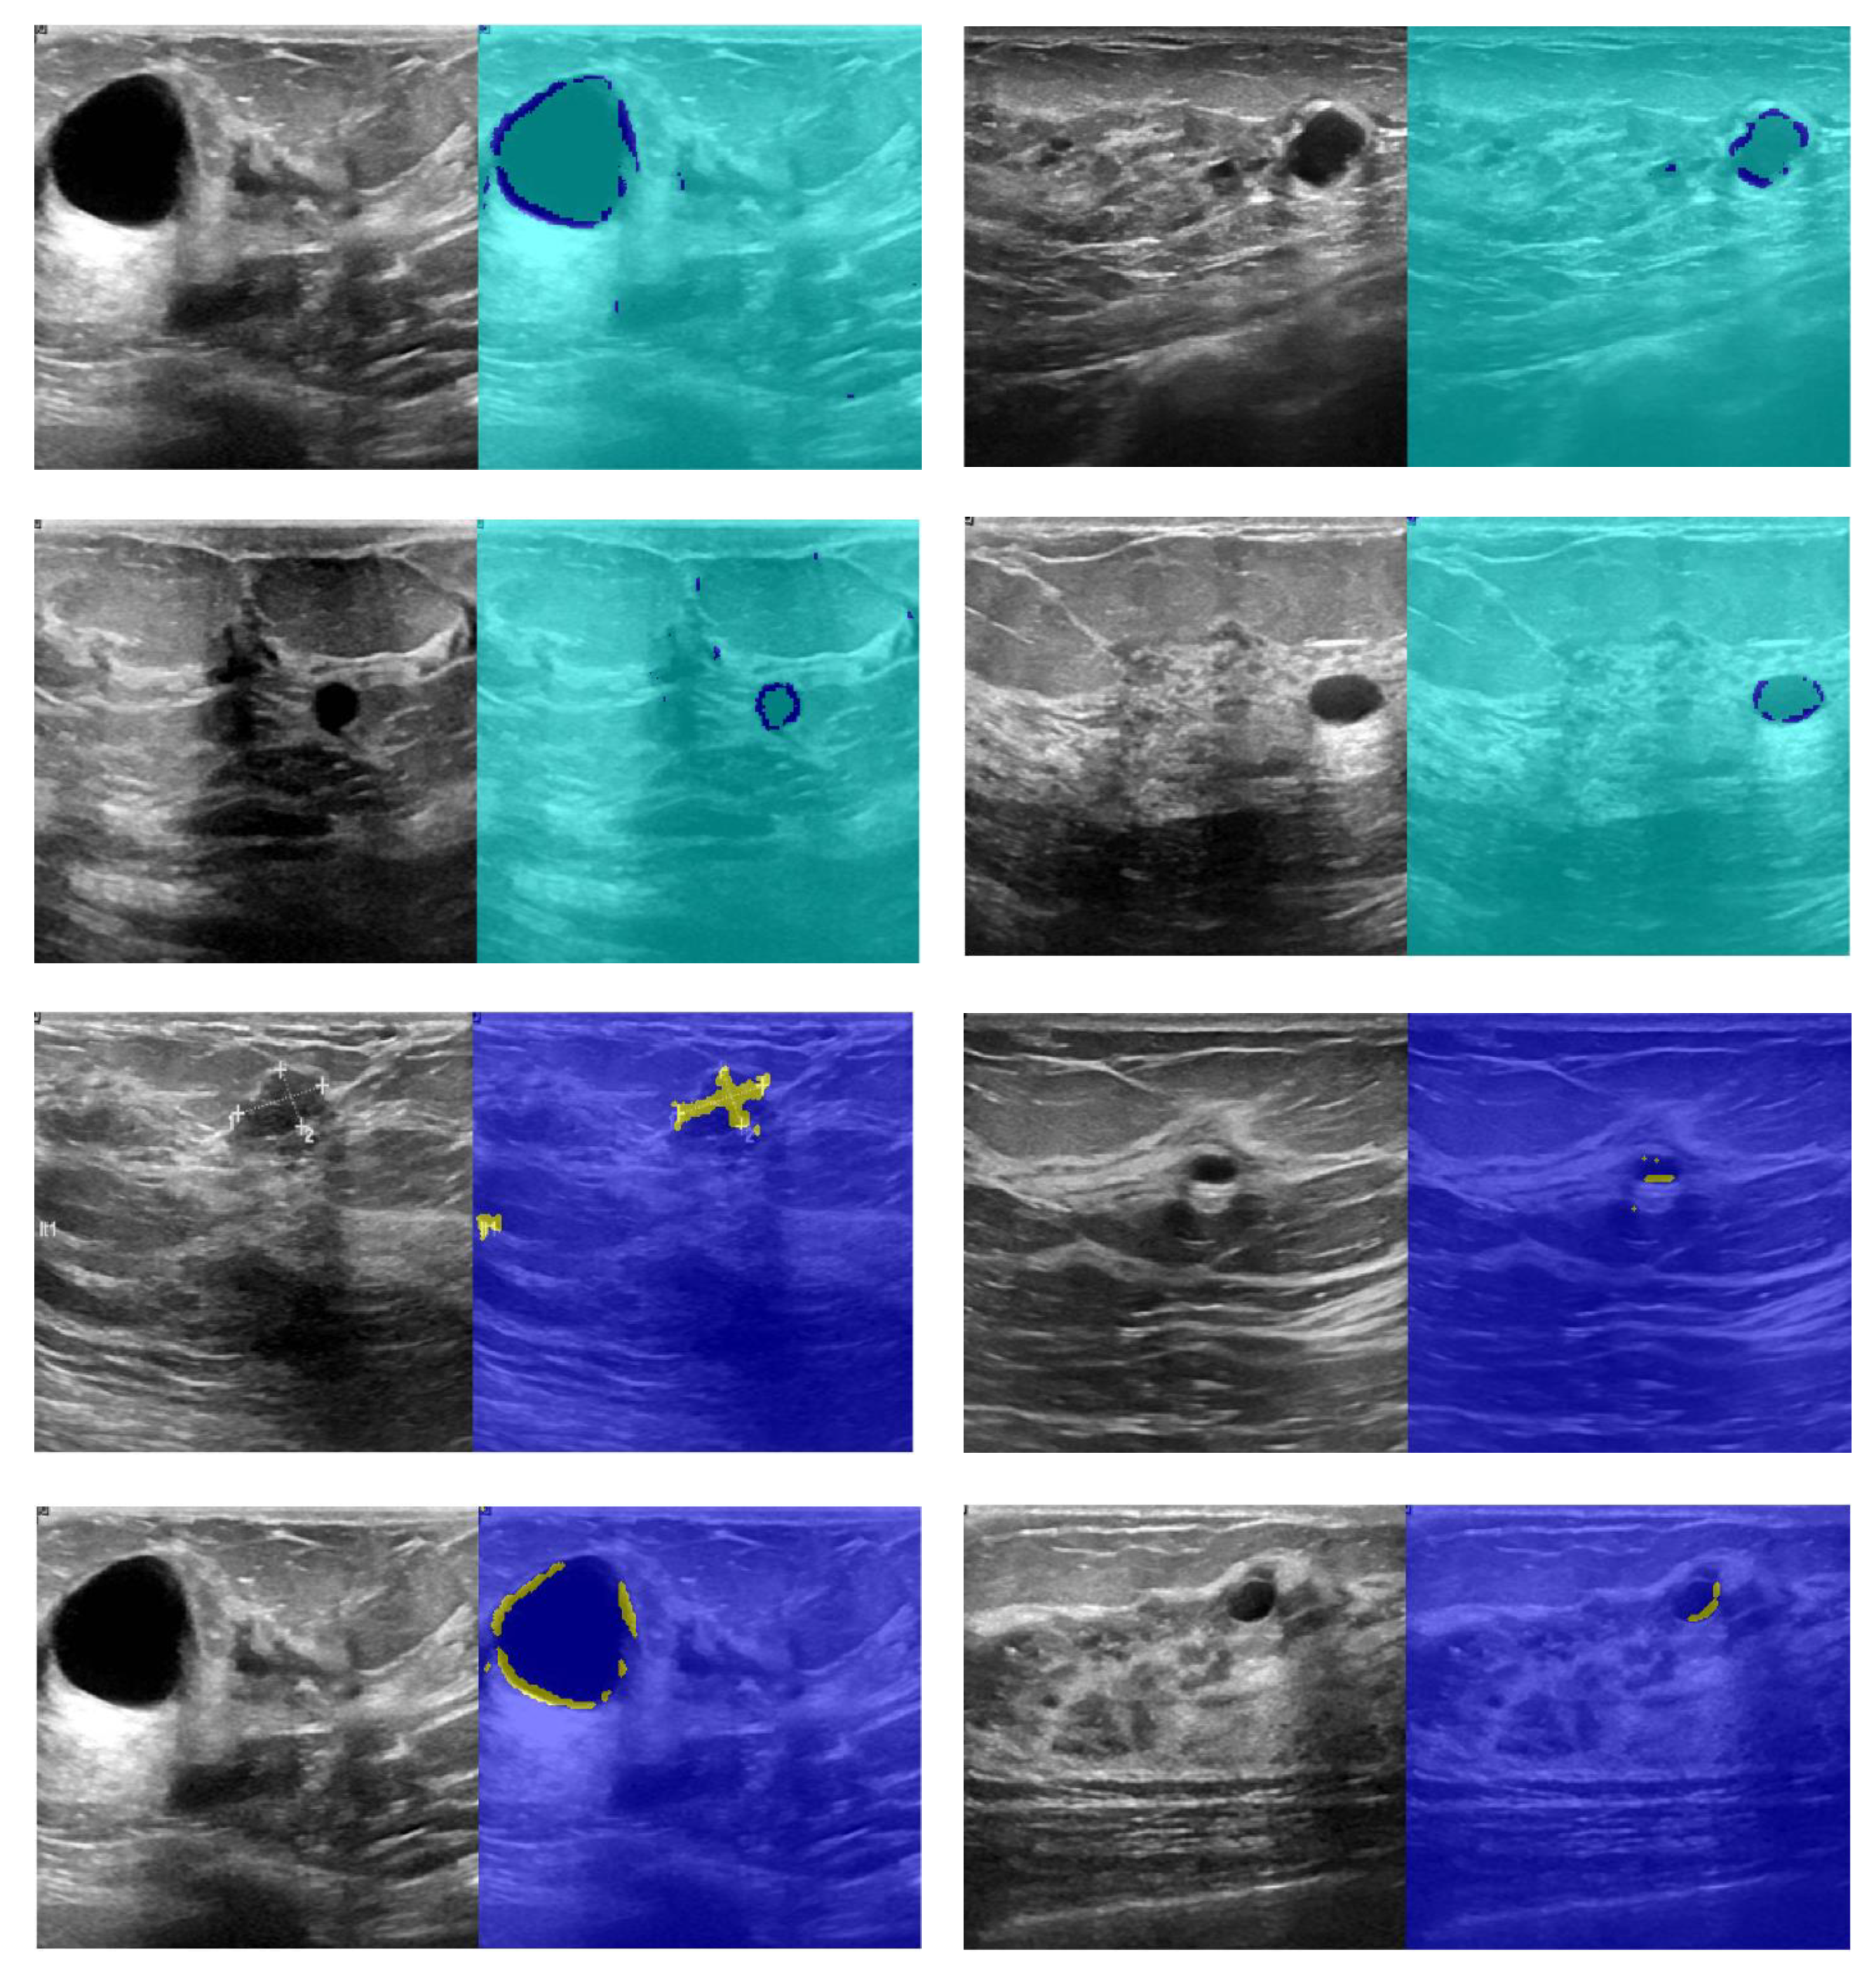

The segmentation results are shown in Figure 10. According to Figure 10, the first and third columns of the input image show the image infected with the cancerous tumor. Moreover, the other side of the image shows the segmentation results. Seventy percent of the images used for network training and 30% for test results start the process. The results of detecting the infected area are shown in the second and fourth columns of Figure 10. The resulting images should look like ground truth images. According to the results, the presented findings are almost similar to the model output. They have correctly identified the location of the tumor. To better increase the output, minor points in the results should be connected with morphological operations. Because the output points of the model were able to identify the approximate location and size of the tumor, we relate the tumor morphology to the original size of cancer. Figure 11 shows the approximate location and size of the tumor after morphological surgery. The results show that the proposed architecture can correctly identify the contaminated area.

Figure 10.

Results of CNN network cancer tumor segmentation.